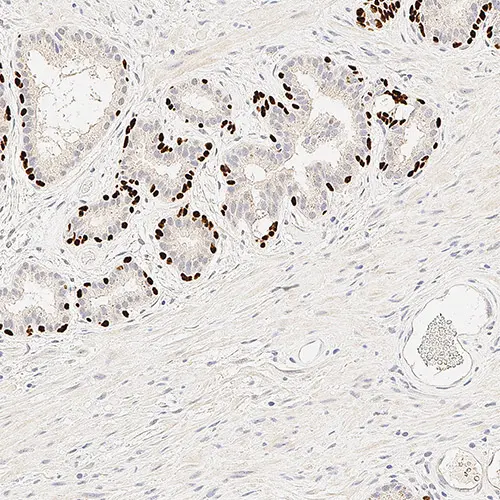

Human skeletal muscle: immunohistochemical staining of HAMLET: HAMLET: clone Ham1/7B6

Dysferlin is the protein product of the 2p13 gene that is defective in patients with Limb-Girdle Muscular Dystrophy type 2B (LGMD2B) and Miyoshi Myopathy (MM). Dysferlin is normally localized to the muscle plasma membrane. In patients with LGMD2B and MM, immunoreactivity to dysferlin is severely reduced or lost. Patients with other neuromuscular conditions demonstrate normal labeling patterns.

HAMLET may require heat-induced epitope retrieval in some cases.

Dysferlin Antibodies are recommended for the detection of specific antigens of interest in normal and abnormal tissues, as an adjunct to conventional histopathology using non-immunologic histochemical stains.